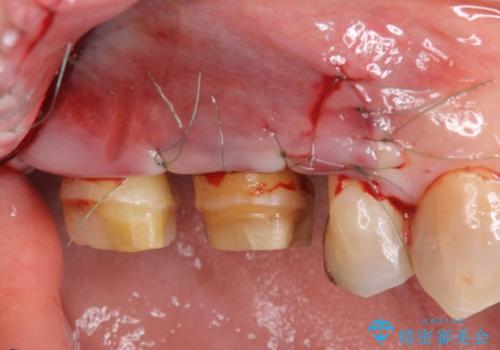

歯周ポケットの除去と再補綴治療

歯周ポケットの除去を歯周外科により行ったのち精度が高く清掃のしやすいセラミック治療による再補綴を行います。

歯を残せるうちに歯周ポケットの除去を行い歯の予後を良くすることができます。